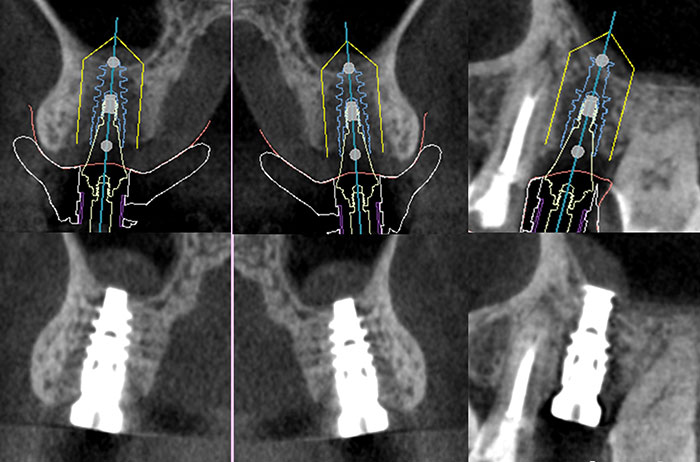

- 歯科用CTスキャナー:骨や神経の状態を三次元で正確に把握

- コンピューターシミュレーション:術前の詳細なインプラント計画

- ガイデッドサージェリー:ズレの少ない計画通りの埋入を実現